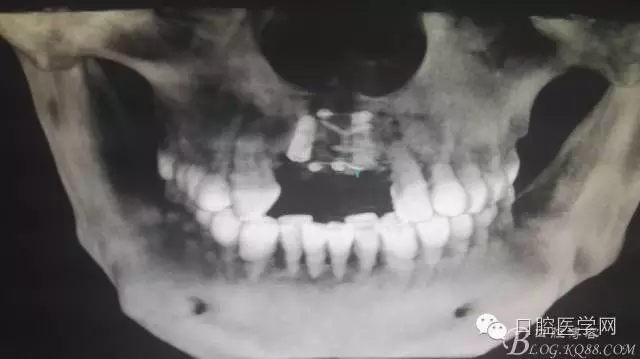

植入種植體左側(cè)3510,右側(cè)4010,植骨Bioss,蓋膜Cytoplast。骨膜減張垂直褥式縫合加間斷縫合。

半年后...

后期的修復(fù)工作由之前的轉(zhuǎn)診醫(yī)生后續(xù)處理,由于GBR過(guò)程骨膜減張導(dǎo)致角化牙齦不足3mm,建議角化牙齦移植改變其更好的牙齦生物型。